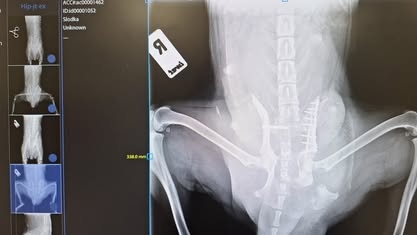

Słodka to sunia która trafiła do mas na prośbę lecznicy weterynaryjnej. Została znaleziona w rowie tuż po połogu lub w poroniła po wypadku.

Jej stan był ciężki ale dzięki Wam i cudownym lekarzom jest tak ♡